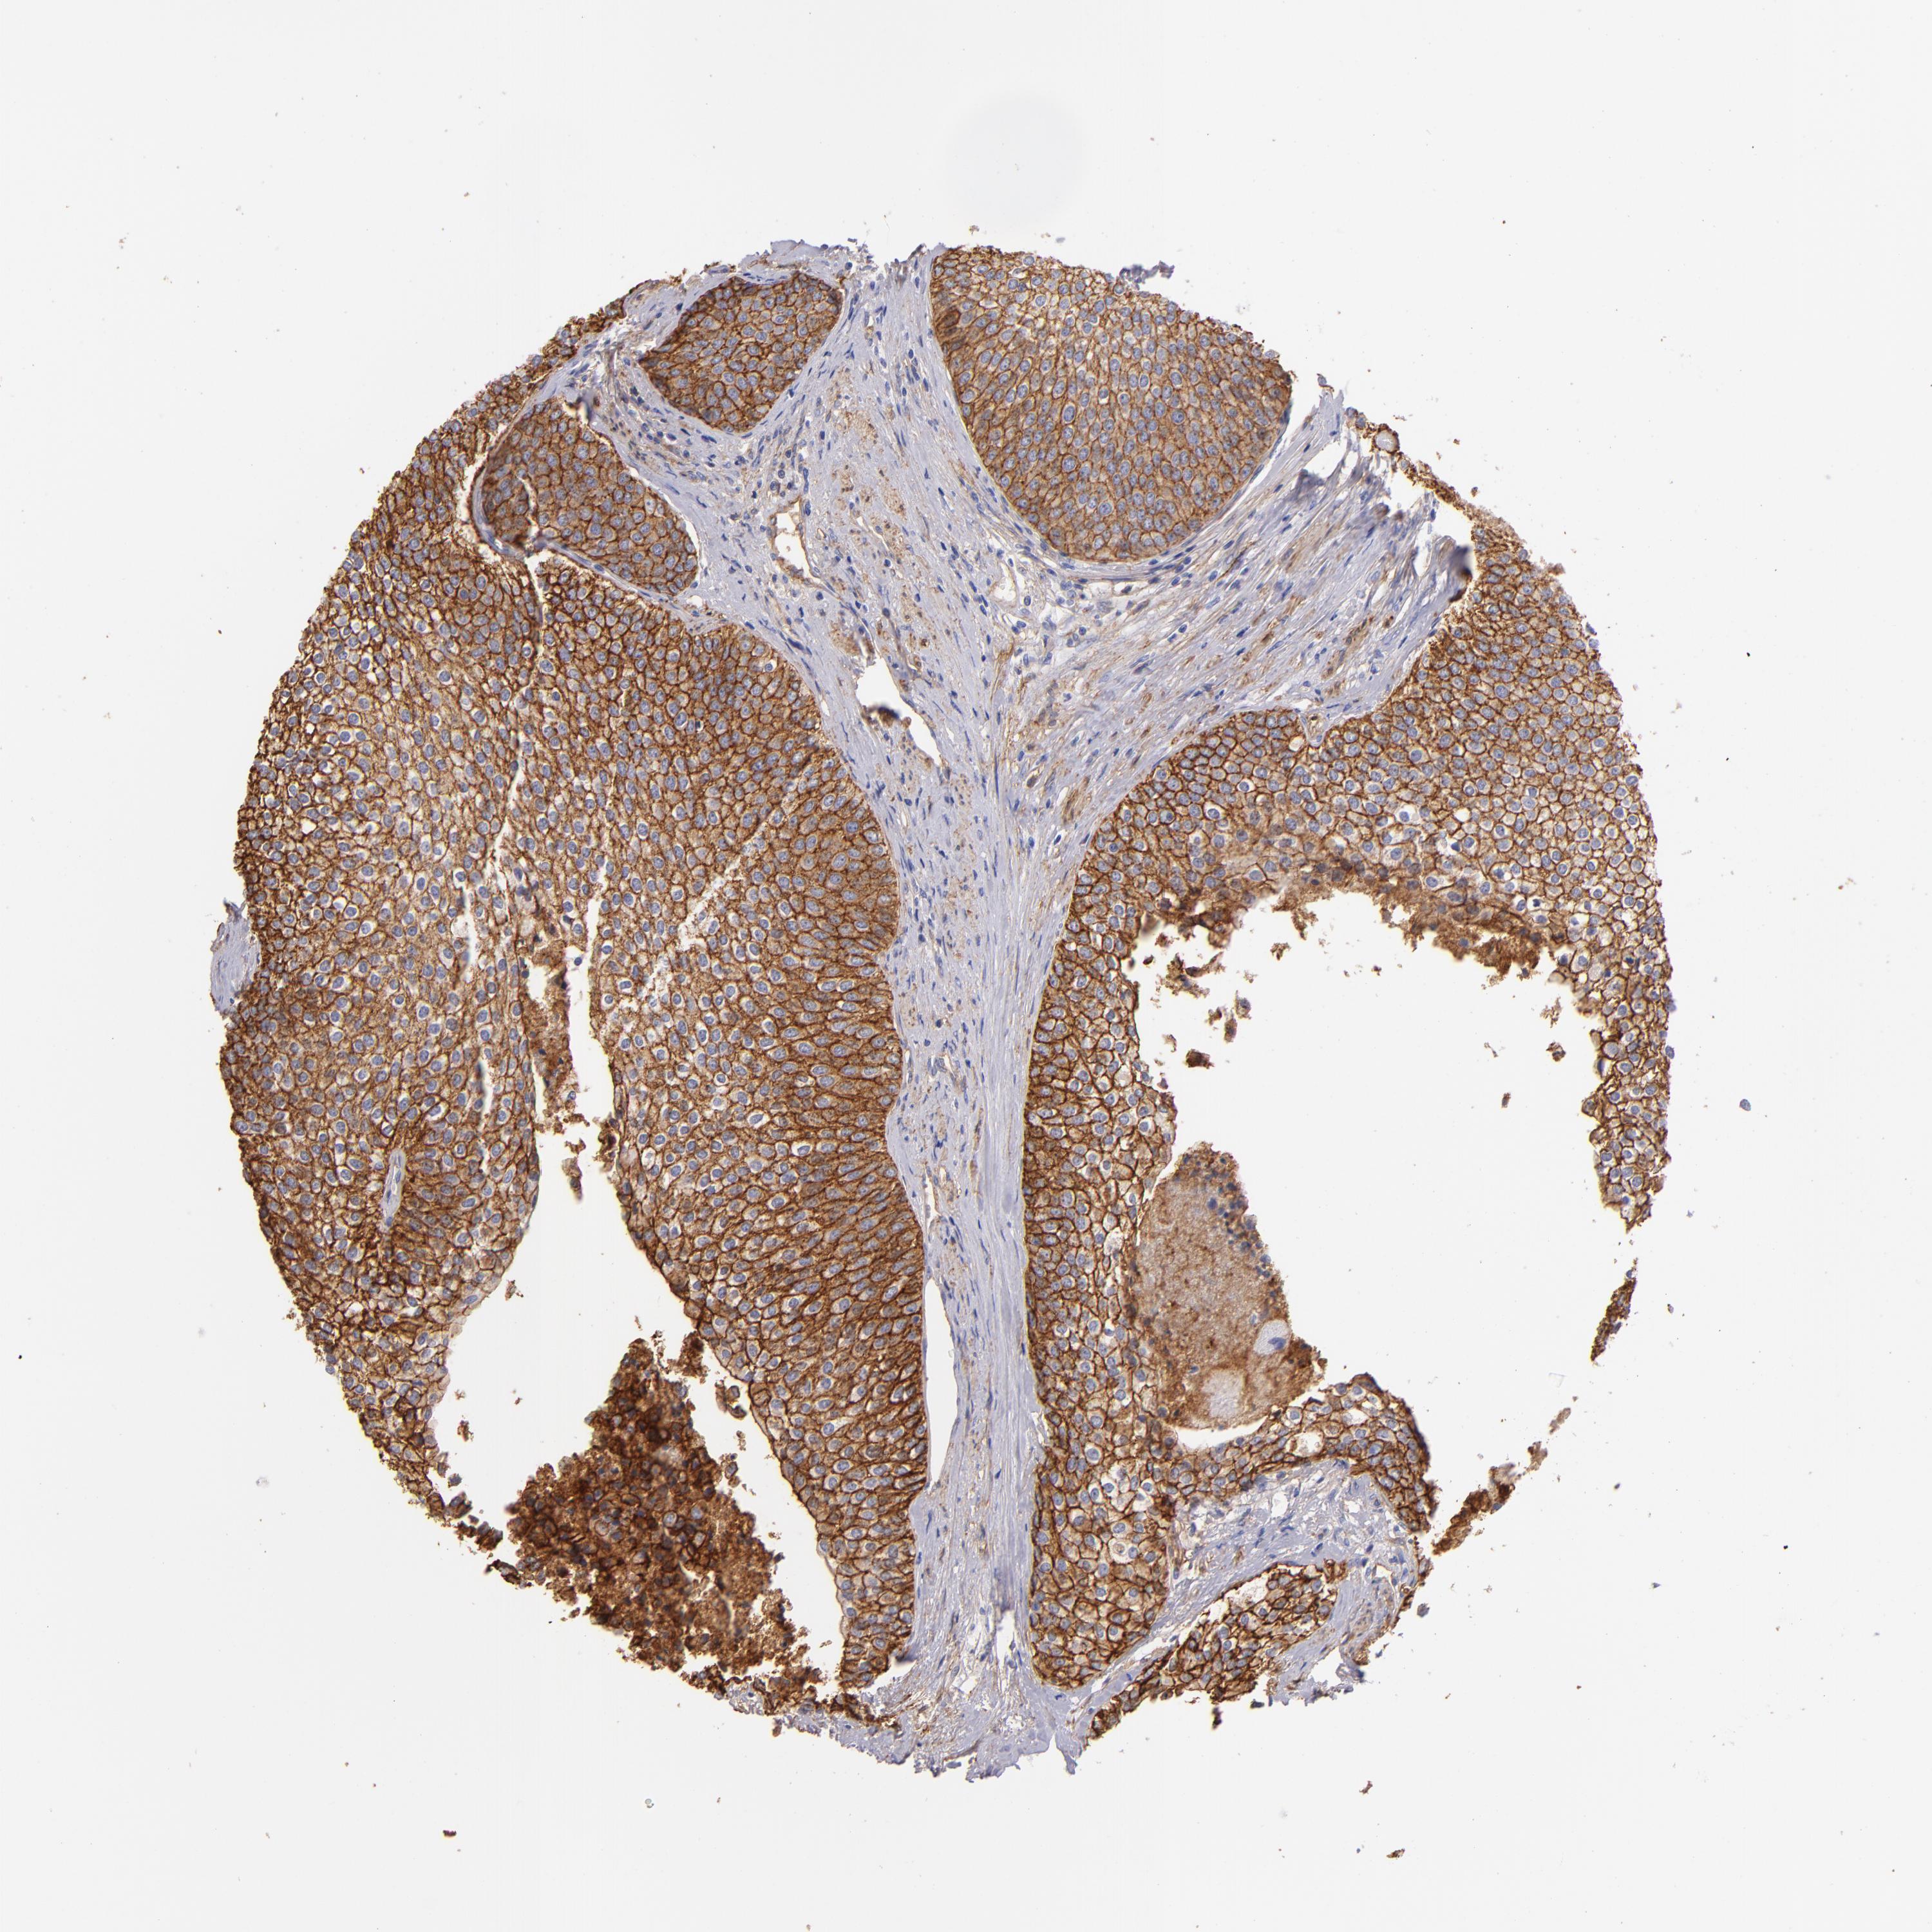

UROTHELIAL CANCER - Protein expressioni

A mouse-over function shows sample information and annotation data. Click on an image to view it in a full screen mode. Samples can be filtered based on level of antibody staining by selecting one or several of the following categories: high, medium, low and not detected. The assay and annotation is described here.

Note that samples used for immunohistochemistry by the Human Protein Atlas do not correspond to samples in the TCGA dataset.

Antibody stainingi

Antibody staining in the annotated cell types in the current human tissue is reported as not detected, low, medium, or high, based on conventional immunohistochemistry profiling in selected tissues. This score is based on the combination of the staining intensity and fraction of stained cells.

Each image is clickable and will lead to virtual microscopy that enables deeper exploration of all samples and also displays staining intensity scores, fraction scores and subcellular localization as well as patient and tissue information for each sample.

Antibody HPA011906

Antibody CAB002428

Urothelial carcinoma, Low grade

Urothelial carcinoma, High grade

Adenocarcinoma, NOS